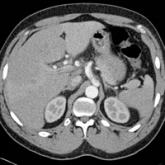

ArticleDissection of the Celiac ArteryAuthor:Eric Iheme, MDPublish date: January 10, 2017A 41-year-old man presented to the ED with a 4-day history of epigastric pain...Read More